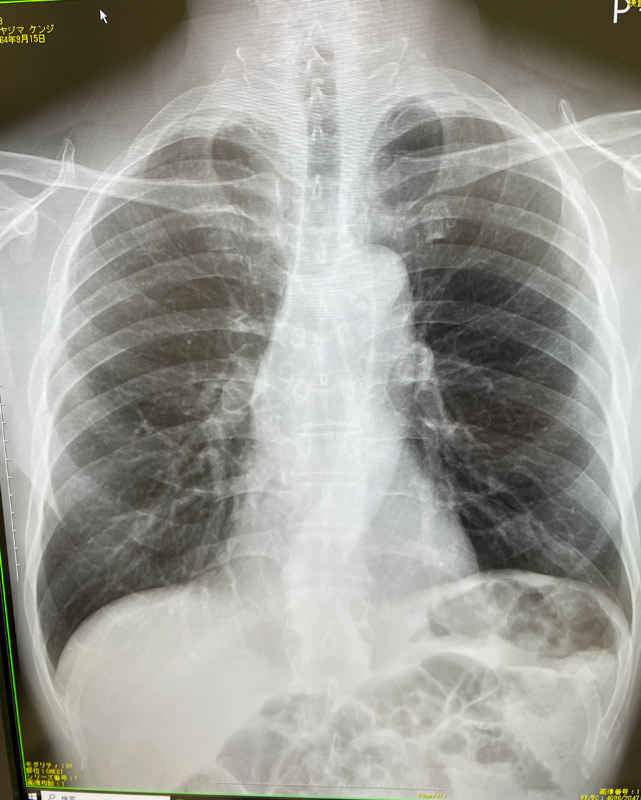

先週、良く分からない微熱が続いていたので撮ってもらった胸部のレントゲン写真です。私の少し前に診た患者さんも似たような症状で、レントゲン撮ったら肺炎起こしていたそうです(比較で見せてもらいました)。

私は何も問題無いそうですが、体調が悪かったのは事実です。念のため、血液検査もしていただいています。平気になっちゃうと大げさだったかと思ってみたりもしますが、週明けに結果を聞きに行ってきます。

しかし、ピラティスで身体のことを勉強した今、あらためで自分の身体見るといろいろと興味深いもんです。背骨、肋骨、鎖骨に肩甲骨、ベンキョーしたとおりです(あたりまえです)。あとは横隔膜はこの辺かなあ、なんて感じです。